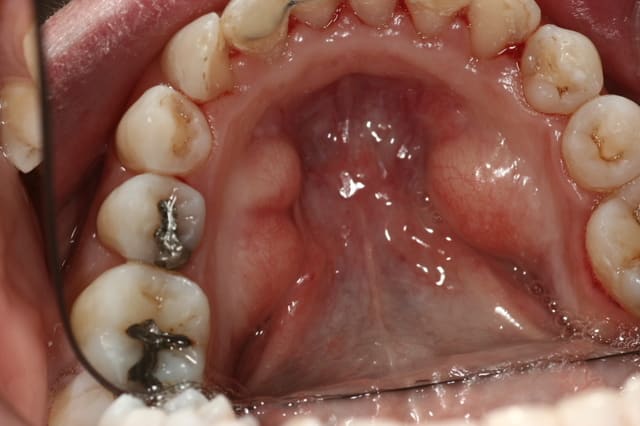

superbe taurus palatin ...

...suivi de tori linguaux.